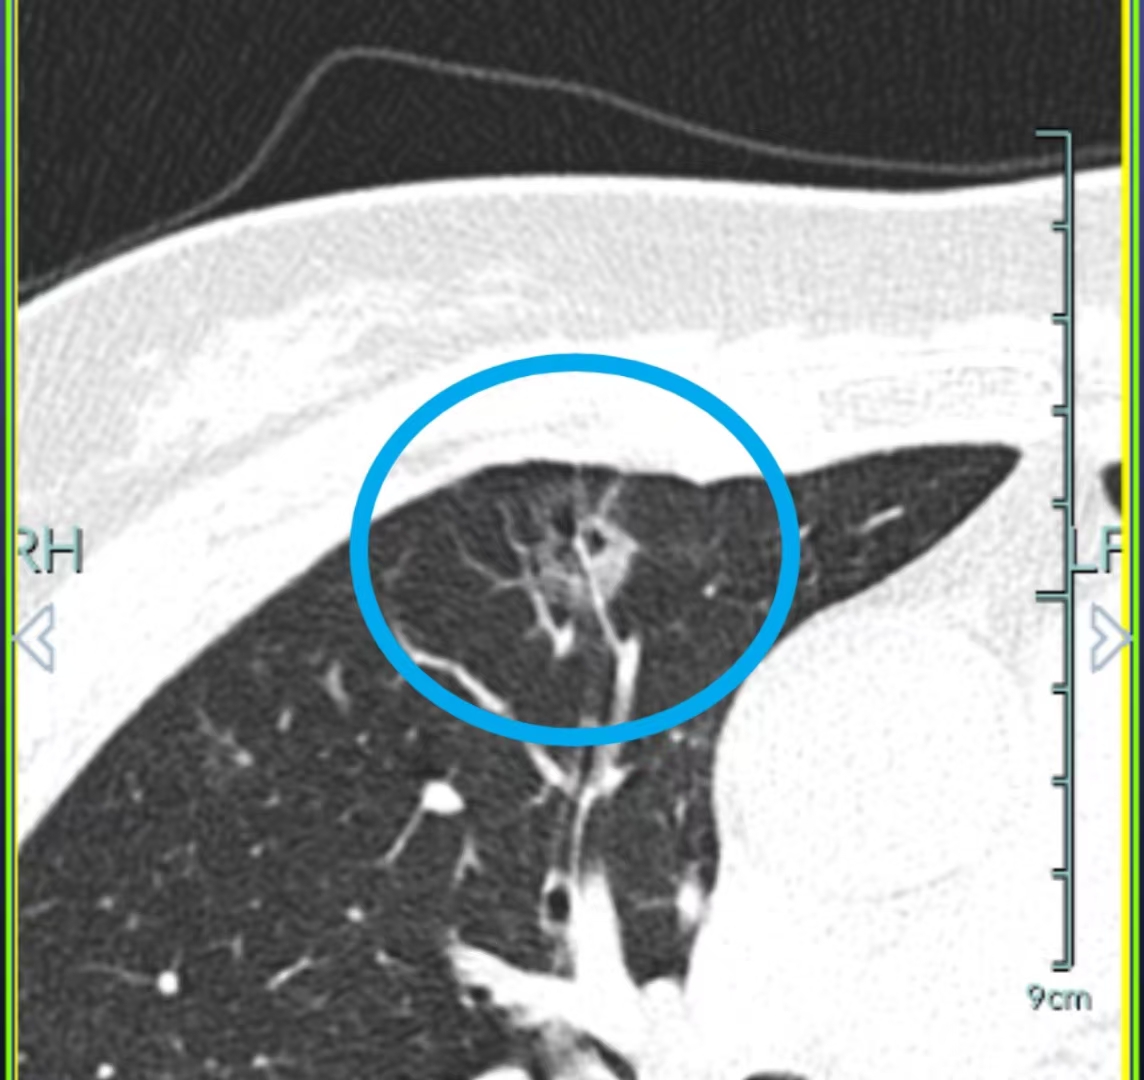

但可別以為X光檢查正常就萬(wàn)事大吉了,這就好比妖怪會(huì)使障眼法,一些較小或位置隱蔽的結(jié)節(jié)就像藏在石頭縫里的小妖怪,X光這個(gè)“照妖鏡”可能就失靈了,這時(shí)候就得請(qǐng)出CT掃描這個(gè)更厲害的“火眼金睛”,確保把這些“小妖怪”都揪出來(lái)。

對(duì)于小結(jié)節(jié)的隨診觀察,薄層CT,也就是我們說(shuō)的高清CT,就像是孫悟空的放大鏡,能把結(jié)節(jié)的變化和細(xì)節(jié)看得清清楚楚,讓那些“小妖怪”無(wú)處遁形。而對(duì)于中央型結(jié)節(jié)或懷疑有淋巴結(jié)轉(zhuǎn)移的情況,平掃CT就像在霧里看花,結(jié)節(jié)、淋巴結(jié)和血管混在一起,難以分辨。

這時(shí)候增強(qiáng)CT就如同孫悟空的金箍棒,一下子就能區(qū)分結(jié)節(jié)或者淋巴結(jié)和周圍血管的關(guān)系,判斷出“妖怪”的具體情況和是否有“小嘍啰”跟著。要是懷疑有遠(yuǎn)處轉(zhuǎn)移的結(jié)節(jié),那PET - CT就像是千里眼,能判斷全身其他器官是否有高代謝的轉(zhuǎn)移灶,看看“妖怪”是不是在其他地方安了“據(jù)點(diǎn)”。